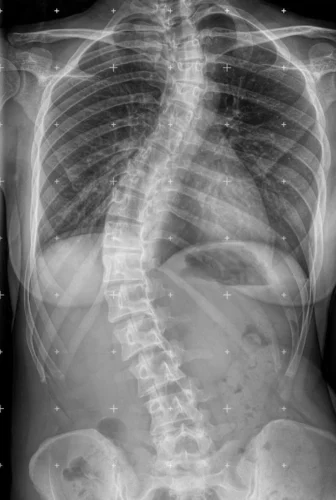

يُعتبر اعوجاج العمود الفقري مجهول السبب عند المراهقين (Adolescent Idiopathic Scoliosis – AIS) من أكثر المشكلات شيوعًا في مرحلة المراهقة، وتلعب الوراثة والعوامل العائلية دورًا مهمًا في ظهوره وتطوره. أظهرت الأبحاث أن ليس فقط شكل العمود الفقري الجانبي (الانحناء) هو المهم، بل أيضًا شكل العمود الفقري من الجانب وتوازن الحوض والعمود الفقري قد يكون لهما دور في انتقال المرض داخل العائلة.

تشير الدراسات إلى أن بعض الأشخاص يولدون ب(انحناء أمامي وخلفي) يجعل العمود الفقري أقل مقاومة للالتواء والدوران، وهذا قد يسهل ظهور الاعوجاج عند المراهقين.

تبين أن آباء الأطفال المصابين بالاعوجاج لديهم عمود فقري أكثر استقامة (Flatter spine) مقارنة بآباء الأطفال الأصحاء.

كانت زوايا الانحناء القطني أقل، أي أن التقوس القطني لديهم كان أضعف.

بعض الفقرات، خاصة من T11 إلى L2، كانت أقل ميلاً للخلف.

هذا النمط يشير إلى أن العمود الفقري عندهم أقل قدرة على مقاومة الدوران، مما قد يفسر انتقال الميل للاعوجاج عند الأبناء.

أظهرت الدراسة أن آباء الأطفال المصابين بالاعوجاج لديهم عمود فقري أكثر استقامة وأقل تقوسًا مقارنة بالآباء الآخرين، مما قد يفسر دورهم في انتقال المرض وراثيًا. بينما لم يظهر فرق واضح عند الأمهات من ناحية شكل العمود الفقري السهمي.